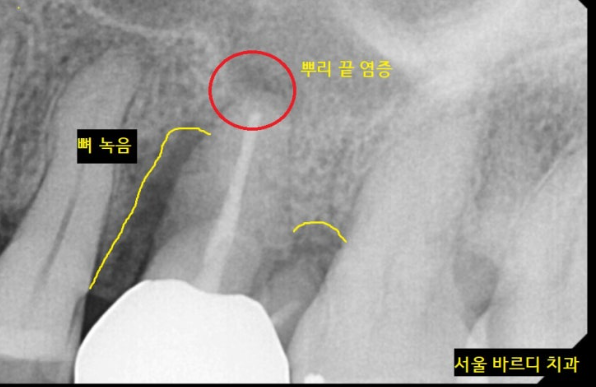

원인 파악을 위하여 전체 x-ray 촬영

역시나 왼쪽 윗니 치아에 문제가 있었습니다.

뿌리쪽에 문제가 있어보여

한 장 더 찍어보았는데요.

뿌리 끝에 염증이 발견되었습니다.

염증이 있어서 어금니가 아프셨던 거네요~~

치아에 염증이 있다 보니

주변 잇몸뼈를 녹은 상황

신경치료도 다 되어있는 상황이라

더 이상 치료할 수 있는 방법이 없었습니다.